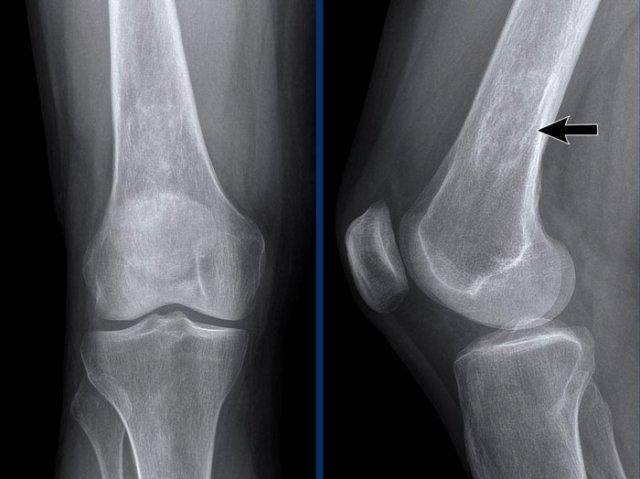

Tại khớp gối, thoái hóa khớp được phân loại theo thang điểm Kellgren và Lawrence.

Thang phân loại này có thể được áp dụng để đánh giá mức độ thoái hóa ở các khớp khác, tuy nhiên nó được thiết kế chủ yếu cho khớp gối.

Thoái hóa khớp gối

Hẹp khe khớp đùi-chày khoang trong mức độ vừa đến nặng, không đối xứng, kèm hình thành gai xương và xơ cứng xương dưới sụn (phân loại Kellgren-Lawrence độ 3-4).

Hình ảnh cho thấy các hạt tophi lan rộng quanh khớp gối ở bệnh nhân gout (đầu mũi tên).

Tại khớp gối, các vị trí này (điểm bám gân khoeo, điểm bám gân tứ đầu đùi, điểm bám dây chằng bên trong – MCL) rất điển hình.

Có tràn dịch khớp mức độ nhẹ.

Hẹp khe khớp có thể do thoái hóa khớp thứ phát.